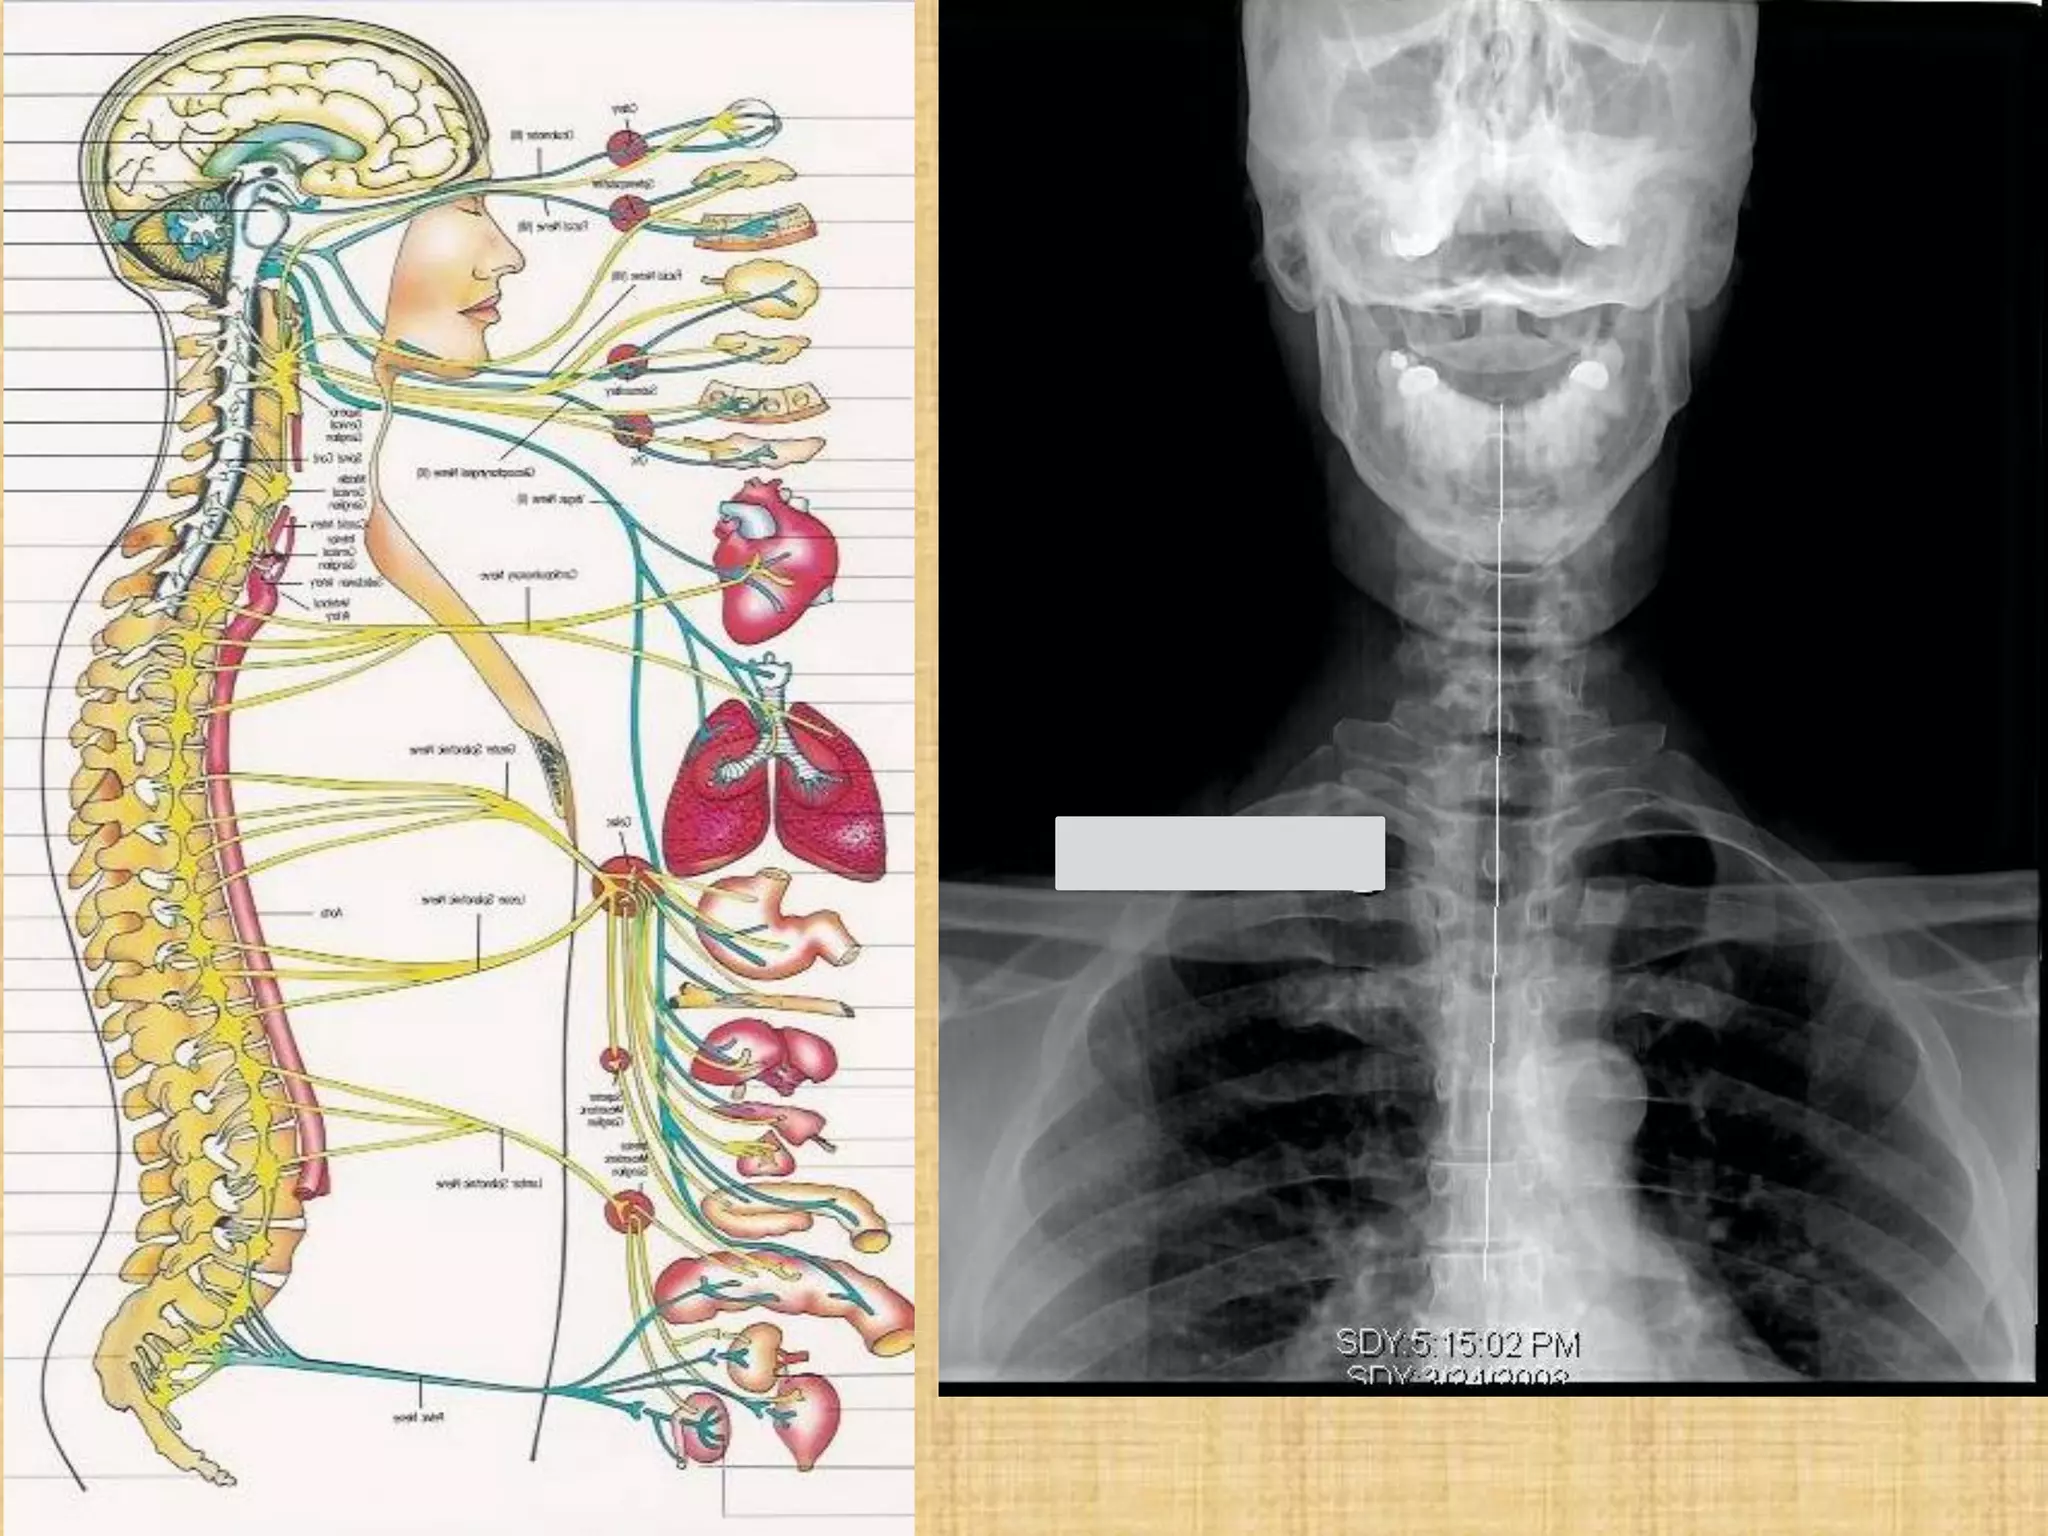

3 signals Cause dis-ease

1. Trauma. Misalignment of the spine can impede the

transmission of the nerve impulses

2. Toxicity. Toxins and poisons can distort the signal’s information

on its path between the nervous system

3. Thought Health is the nervous system’s ability to accurately

perceive environmental information and selectively engage

appropriate, life-sustaining behaviors.

The nervous system

controls and coordinates all

functions of the body. This

includes breathing, sleeping

digestion, and elimination.

Gray’s Anatomy, pg. 4

3 signals Causedis-ease 1. Trauma. Misalignment of the spine can impede the transmission of the nerve impulses 2. Toxicity. Toxins and poisons can distort the signal’s information on its path between the nervous system 3. Thought Health is the nervous system’s ability to accurately perceive environmental information and selectively engage appropriate, life-sustaining behaviors. If a mind misinterprets environmental signals and generates an inappropriate response. A thought could be enough to undermine an entire system , misperceptions can be lethal.